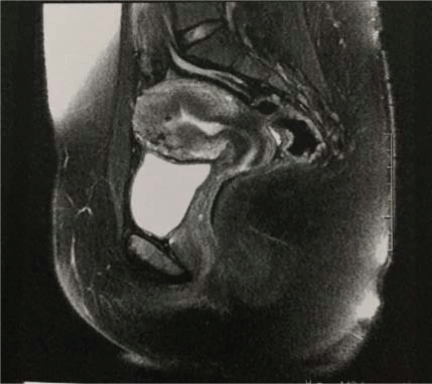

A 22 years old nulligravid female, without comorbidities or past pelvic surgery, presented incapacitating dysmenorrhea and menorrhagia for about a year. Pelvic magnetic resonance imaging (MRI) showed an overall increase in uterine volume (229 cm3) with diffuse thickening of the junctional zone in the anterior wall, measuring up to 53 mm. These findings were compatible with adenomyosis (Figure 1). The CA 125 level was 200.7 U/ml.

Figure 1: MRI before surgery showing an overall increase in uterine volume with thickening of the junctional zone.